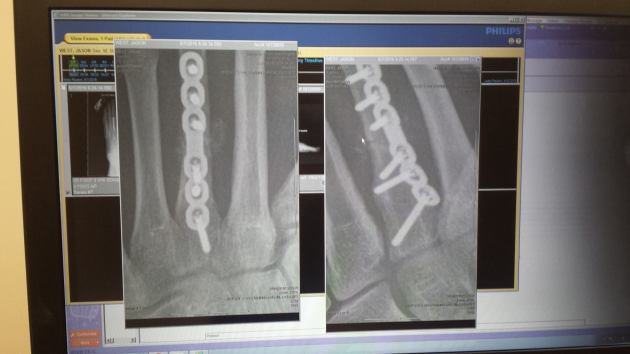

It was the day of the race. Biking and swimming felt completely fine. Then, 400 meters into the 10K run, I felt something snap in my foot, followed by searing pain. For 100 meters I thought I would have to drop out of the race. Then, something amazing happened. My stride came back and I fought through the pain and finished the 10K. After the run, the pain was so severe I couldn’t walk, but still I made my way home. By then, the pain was so intense that I headed to the emergency room. The X-rays of my foot didn’t look good, and the doctors determined that I needed surgery the next day.